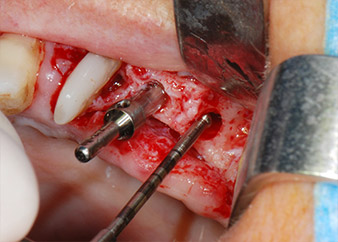

One month later, on the day of surgery, pain and inflammation at tooth 24 were minimal, but mobility of Miller class 2 was still present. After opening the flaps and cleaning the periapical and peri radicular infected tissue, the extent of the bone defect became obvious (Figs. 2 and 3).

total loss of bone and attachment

Fig. 2 and 3: After raising flaps, one month after endodontic revision and initiation of full-mouth periodontal therapy, the buccal root of tooth 24 showed a total loss of bone and attachment.

However, we maintained our initial plan to retain both teeth as temporary bridge abutments during the six-months osseointegration period of the implants. At reentry, the situation would have to be reassessed. First, in an attempt to manage the endo-perio problem, the remaining root surface was carefully debrided with piezoelectric equipment (Piezomed, W&H, used with the spatula-shaped insert S1, originally designed for erosion of the lateral sinus wall) (Fig. 4).